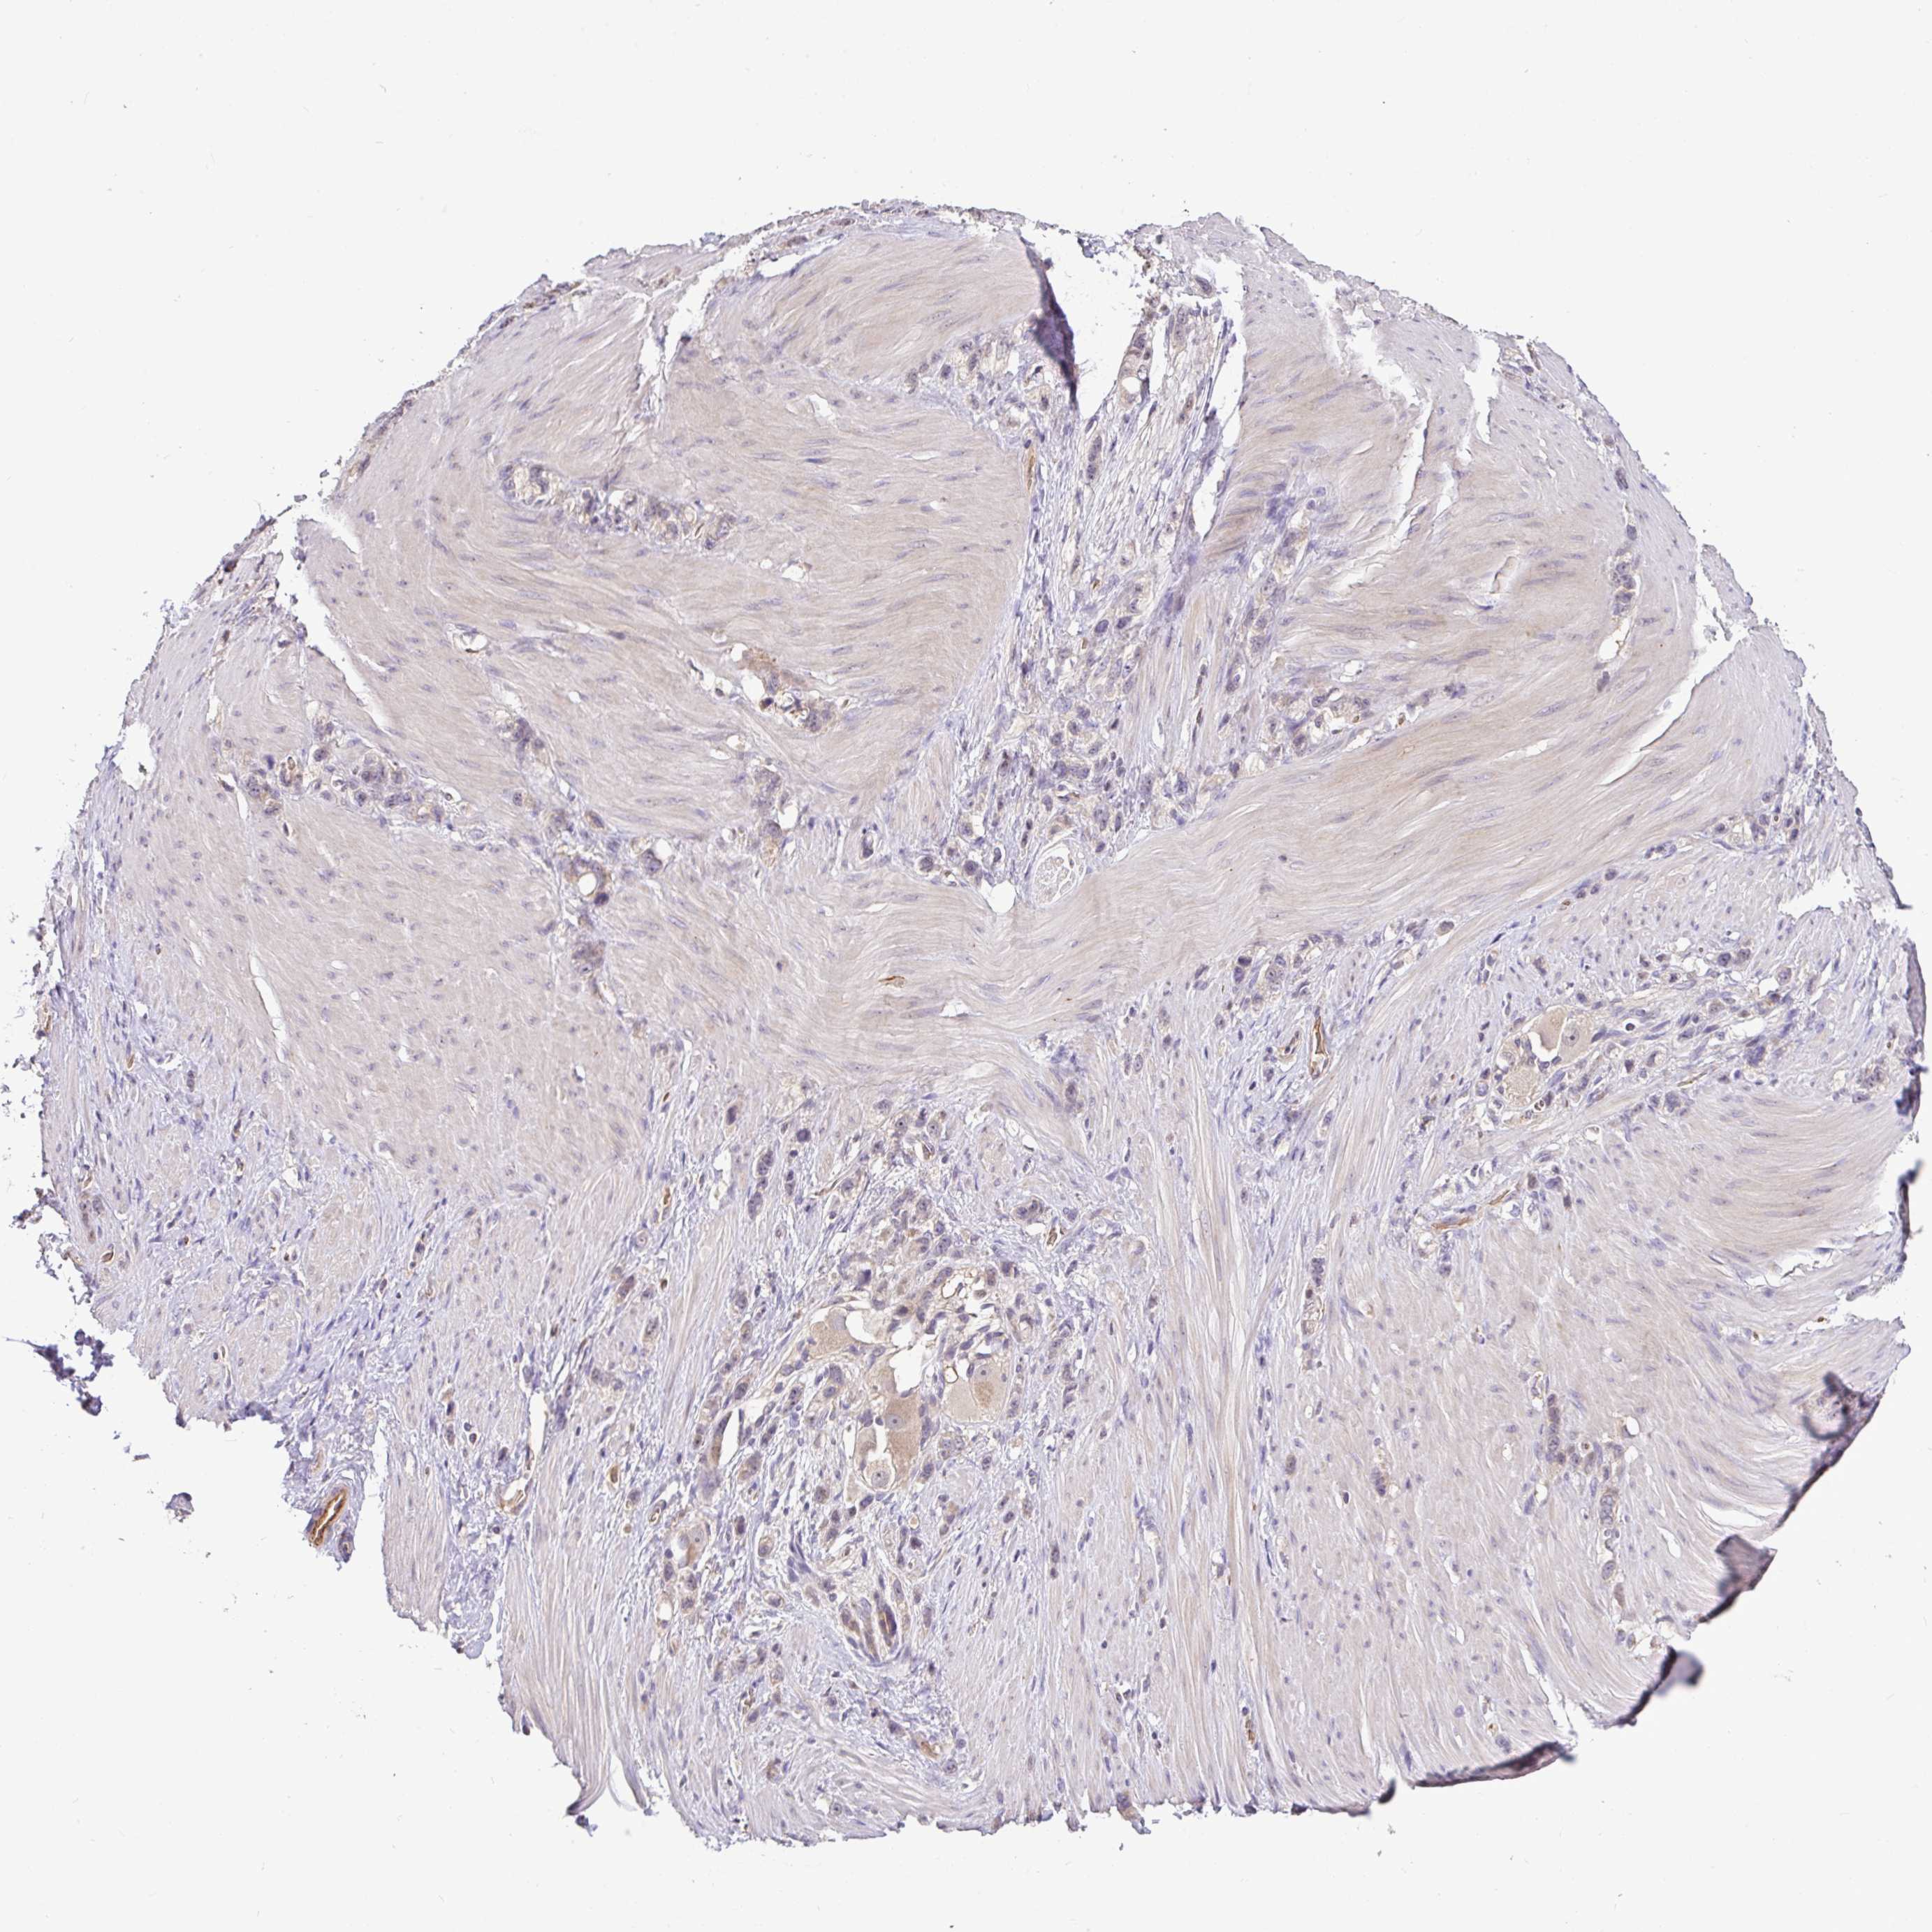

STOMACH CANCER - Protein expressioni

A mouse-over function shows sample information and annotation data. Click on an image to view it in a full screen mode. Samples can be filtered based on level of antibody staining by selecting one or several of the following categories: high, medium, low and not detected. The assay and annotation is described here.

Antibody stainingi

Antibody staining in the annotated cell types in the current human tissue is reported as not detected, low, medium, or high, based on conventional immunohistochemistry profiling in selected tissues. This score is based on the combination of the staining intensity and fraction of stained cells.

Each image is clickable and will lead to virtual microscopy that enables deeper exploration of all samples and also displays staining intensity scores, fraction scores and subcellular localization as well as patient and tissue information for each sample.

Antibody HPA056632

Staining

High

Medium

Low

Not detected

Intensity

Strong

Moderate

Weak

Negative

Quantity

>75%

75%-25%

<25%

None

Location

Nuclear

Cytoplasmic/membranous

Cytoplasmic/membranous,nuclear

Adenocarcinoma, NOS